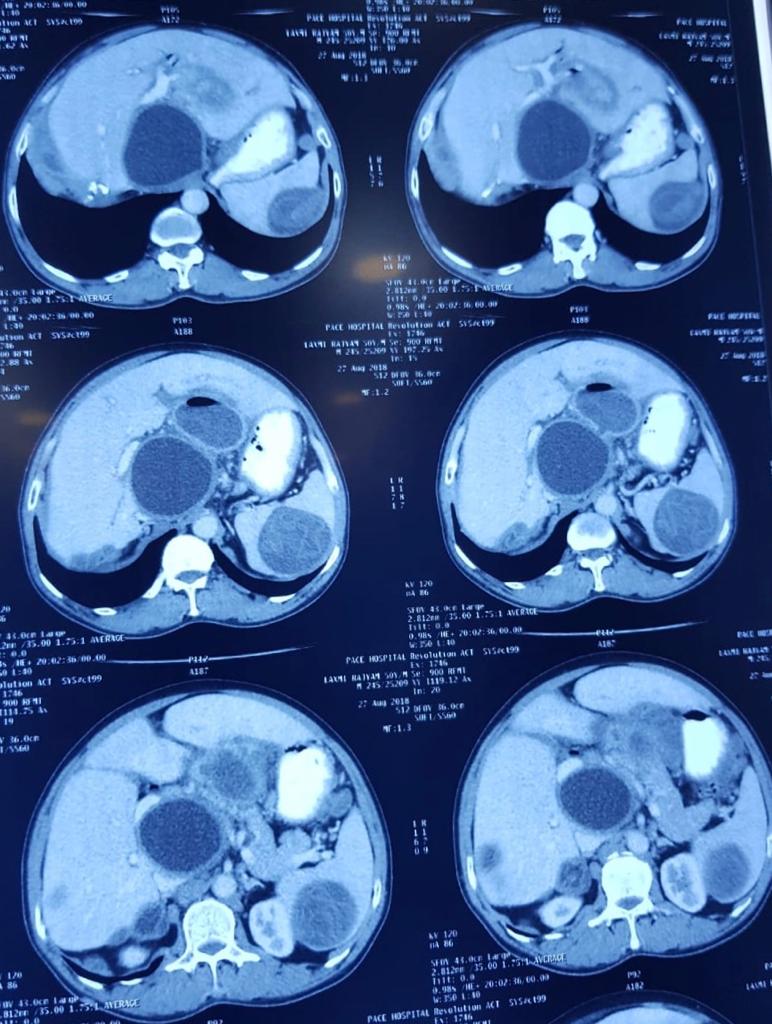

Child’s A CLD with HUGE gastric varices uncontrolled by Endoscopic glue and attempted EUS coiling. One salvage option would be TIPSS with balloon vascular occlusion but due to logistics we went for modified sugiura procedure. Splenectomy + Gastro esophageal devascularisation with anterior Gastrotomy and overseeing of gastric varices with pyloroplasty. Images show 1 CECT showing large gastric fundal varices. 2,3,4 Gastro Esophageal devasc 5, 6 Large fundal varices before and after oversewing. 7. Anterior gastrotomy 8. Pyloroplasty. Postoperative recovery was uneventful.